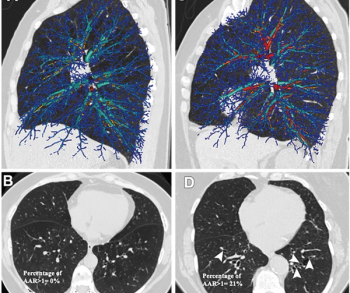

In their review of follow-up chest computed tomography (CT) scans, researchers from Wuhan, China found that nearly 40 percent of patients had interstitial lung abnormalities two years after having COVID-19.